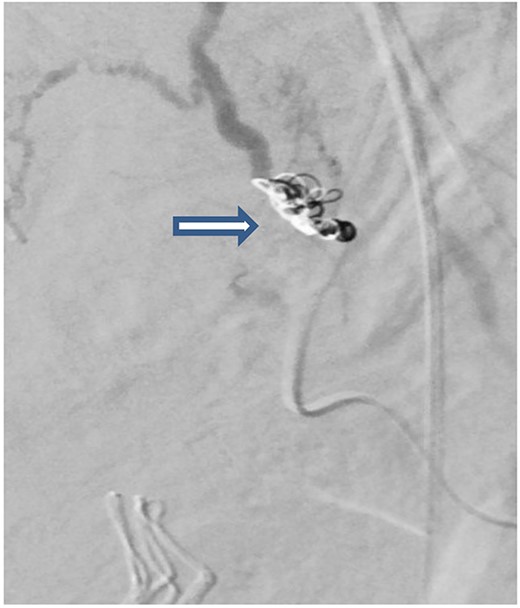

The case was again discussed between trauma and obstetric teams for possible need for interventional radiology consultation. Angiogram showed tortuous arteries with parenchymal blush in the right side of uterine wall, which was related to postpartum status. Gelfoam embolization of the right uterine artery was done to reduce the flow. On the other side, angiogram detected a pseudoaneurysm measuring ~7 mm (Fig. 3). Multiple vortex coils were used to obliterate the feeding vessels and post embolization angiogram showed satisfactory results (Fig. 4).

Post embolization angiogram showed satisfactory results after multiple Vortex coils were used to obliterate of feeding vessels.